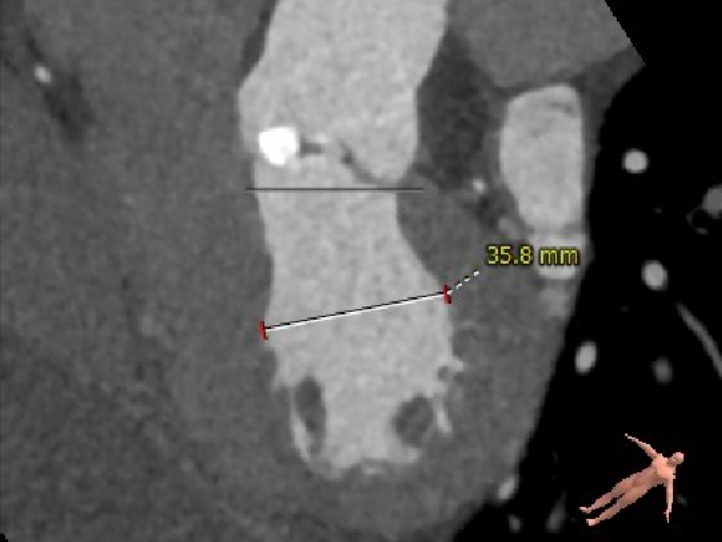

冠脉高度测量

左冠开口高度15.5mm

右冠开口高度20.0mm